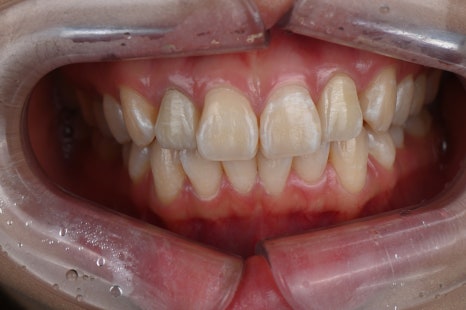

시술명 : 라미네이트

왼 : 시술 전 / 오 : 시술 후 5일 경과